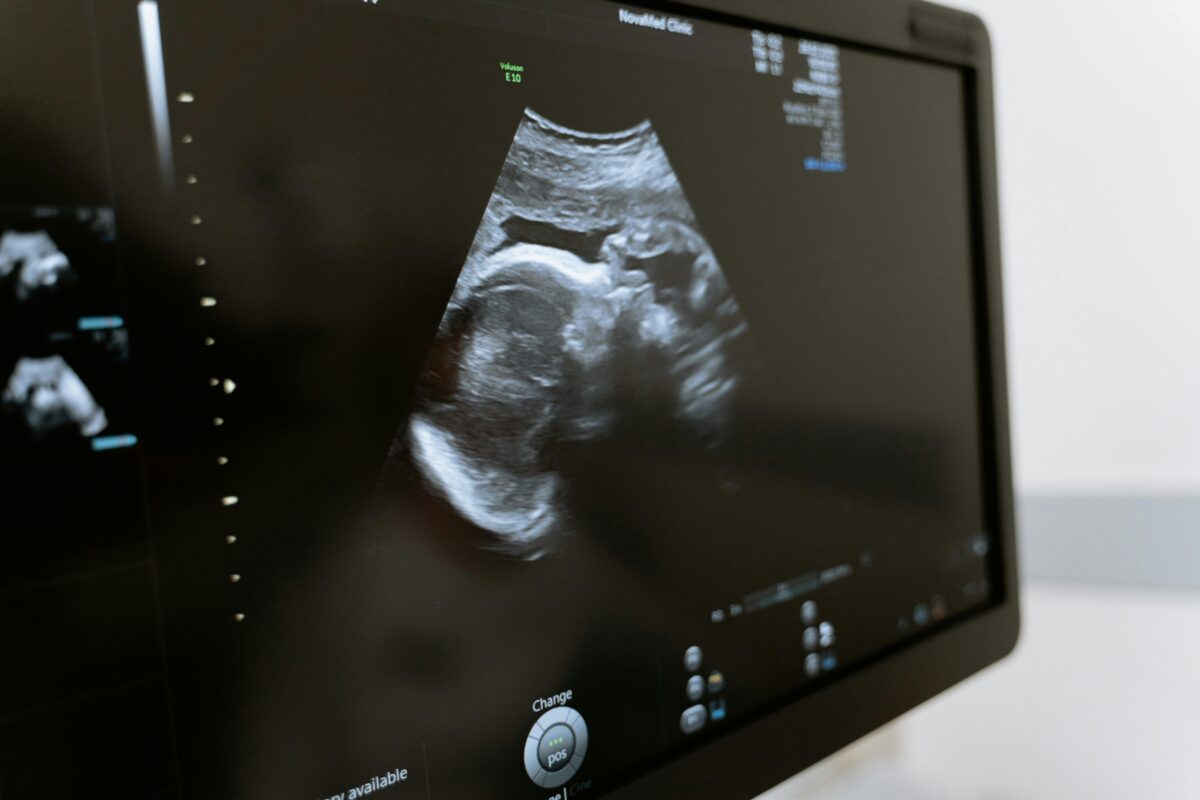

A pesar de que la mujer es quien protagoniza la labor de parto, en ocasiones se le niega la posibilidad de decidir sobre su propio cuerpo al momento de dar a luz. Sucede en clínicas y hospitales, donde la dignidad puede pasar a un segundo plano entre la prisa del personal médico y la rutina. Pero todavía hay mujeres que luchan por devolver el derecho a un parto elegido y respetado en Venezuela

Esta responsabilidad recae en figuras como la ginecobstetra y la doula. El equipo de El Diario entrevistó a una profesional de cada rama para conocer su perspectiva para asegurar que las mujeres tomen decisiones informadas en un momento tan importante, y a la vez vulnerable, como lo es el momento de dar a luz.